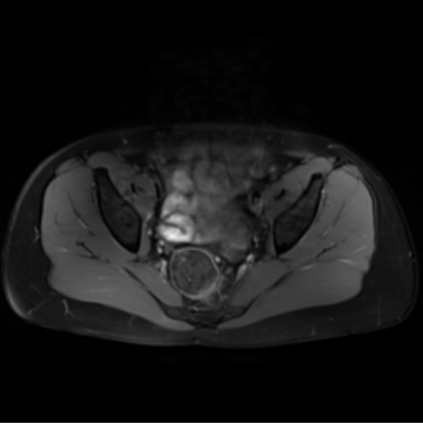

Motion artifacts are a primary source of magnetic resonance (MR) image quality deterioration with strong repercussions on diagnostic performance. Currently, MR motion correction is carried out either prospectively, with the help of motion tracking systems, or retrospectively by mainly utilizing computationally expensive iterative algorithms. In this paper, we utilize a novel adversarial framework, titled MedGAN, for the joint retrospective correction of rigid and non-rigid motion artifacts in different body regions and without the need for a reference image. MedGAN utilizes a unique combination of non-adversarial losses and a novel generator architecture to capture the textures and fine-detailed structures of the desired artifacts-free MR images. Quantitative and qualitative comparisons with other adversarial techniques have illustrated the proposed model's superior performance.